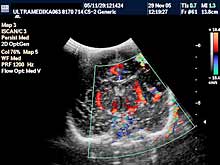

B) Ultrazvučni pregled abdomena-trbuha

Ovaj pregled se savetuje da se

radi bez obzira da li postoji klinička potreba ili ne. Inače najčešća

indikacija je povraćanje u mlazu koja obično počinje oko 3 nedelje

života!

Vrsta pregleda:

- 2D i 3D organa stomaka,

- Broad band CD vaskularizacije

organa a po potrebi primenom CPA i CPD i 3D CPA

- UZ sonda od 5-12 MHz.

- Kompjuterski program je obavezan za ove preglede

u dece!